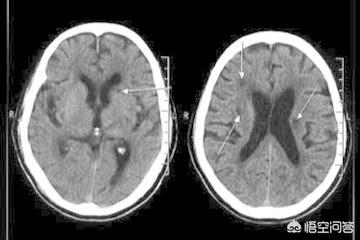

- Toutefois, outre les différences de présentation clinique, il arrive parfois que l'on ne soit pas en mesure d'évaluer l'efficacité du traitement.Le diagnostic ne peut pas être établi uniquement sur la base des symptômes cliniques.Les résultats doivent également être obtenus à l'aide de tests d'imagerie, tels queCT crânien et IRM crânienne. Qu'il s'agisse d'un infarctus lacunaire ou d'un infarctus cérébral, il n'y a pas de changement significatif au scanner crânien dans les 24 heures car le tissu cérébral est seulement ischémique et hypoxique, et il n'y a pas de nécrose liquéfiée du tissu cérébral infarci. Il est possible de l'identifier dans une certaine mesure lorsqu'il date de moins de 24 heures. Dans la phase aiguë des symptômes, l'IRM crânienne est le premier choix d'examen en clinique. Il existe différentes séquences d'IRM, et différentes séquences d'IRM peuvent être utilisées pour réaliser des examens pertinents pour différents cas.Pour le diagnostic de l'infarctus cérébral, les séquences DWI peuvent être très intuitives pour clarifier la situation.。

(3) Examen : tomodensitométrie ou examen magnétique nucléaire de la tête, le meilleur étant l'examen magnétique nucléaire, qui permet de trouver des foyers caverneux dans les parties correspondantes du cerveau.

Le diagnostic d'infarctus cérébral et d'infarctus cérébral lacunaire doit être précisé par un scanner ou une IRM cérébrale, car l'hémorragie cérébrale et l'infarctus cérébral ont les mêmes manifestations et il n'est pas possible de juger sur la base des manifestations.